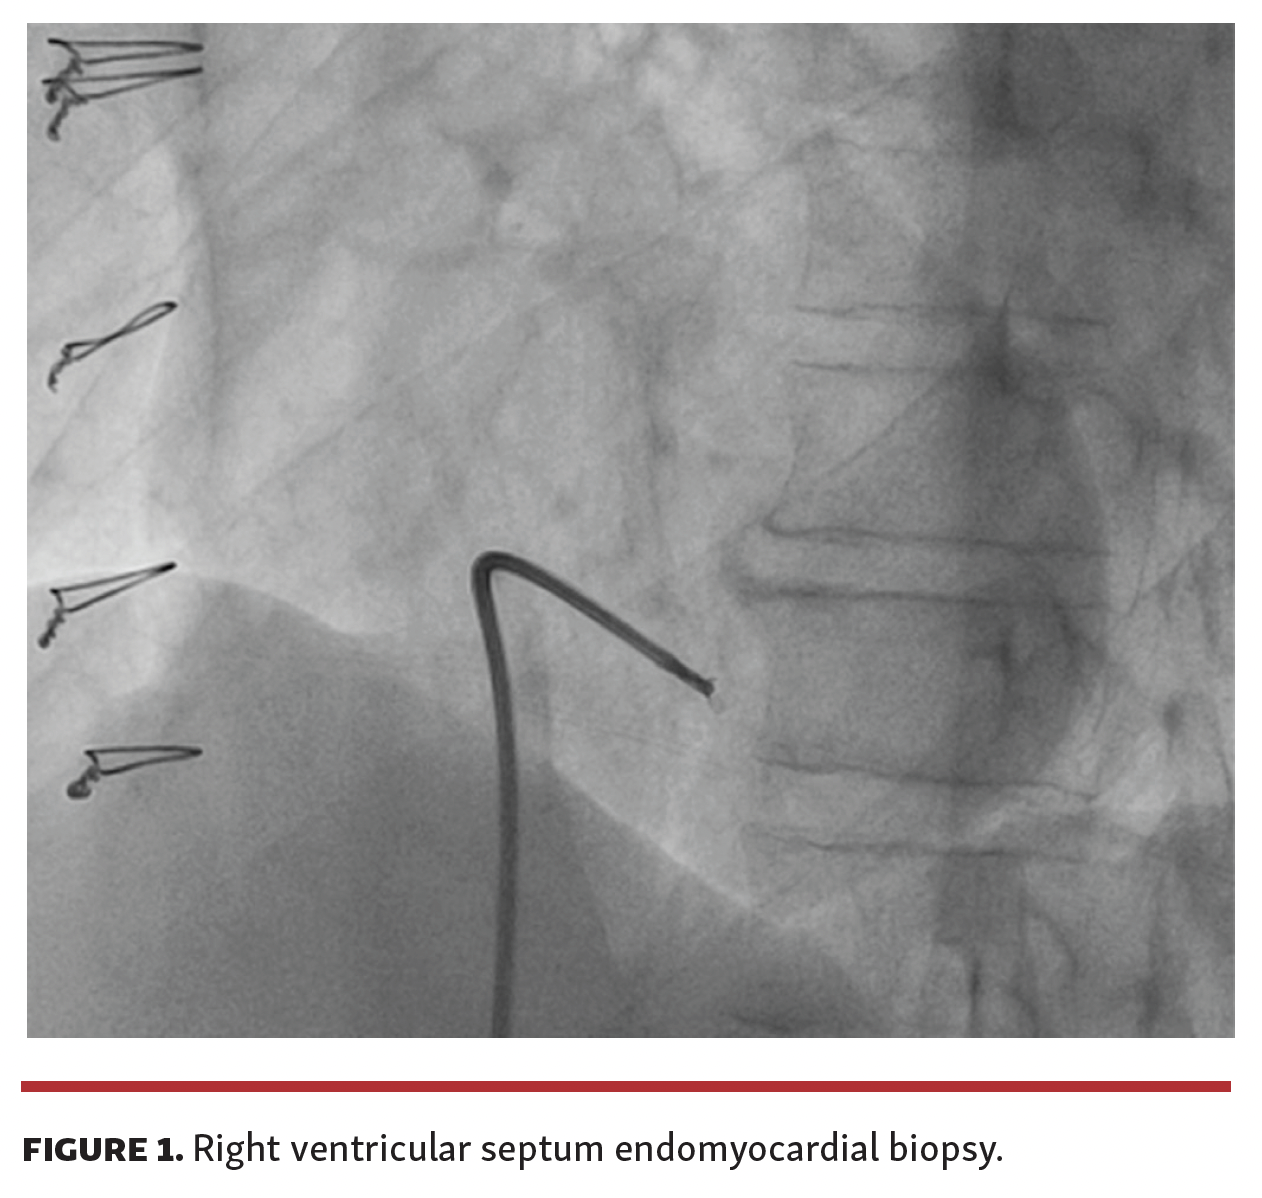

A 69-year-old male patient underwent coronary angiography for evaluation of cardiac ischemia. He had a history of chronic heart failure due to Chagas disease and underwent a heart transplant in 2018. During follow-up, he remained asymptomatic and was regularly subjected to right ventricle endomyocardial biopsies (Figure 1) with no history of graft rejection.